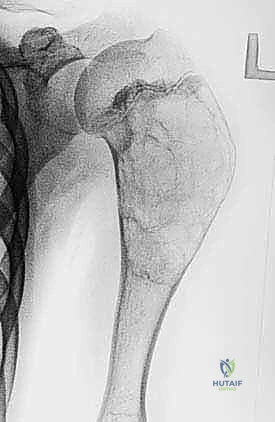

حتى الأورام الحميدة، مثل الورم ذو الخلايا العملاقة (Giant Cell Tumor) أو الأورام الغضروفية (Chondroblastoma)، يمكن أن تكون "عدوانية محلياً". هذا يعني أنها تنمو وتأكل العظم المحيط بها، مما يضعف الهيكل العظمي ويؤدي إلى كسور مرضية، ويهدد بانهيار المفصل القريب. هنا يكمن التحدي: كيف نزيل الورم بالكامل دون تدمير العظم السليم المتبقي؟

- التورم والكتل: ظهور تورم ملحوظ أو كتلة صلبة محسوسة فوق العظم أو بالقرب من المفصل.

بناءً على التقييم الدقيق (الأشعة السينية، الرنين المغناطيسي، الخزعة)، يحدد الأستاذ الدكتور محمد هطيف الخطة العلاجية الأنسب، والتي تتدرج كالتالي: